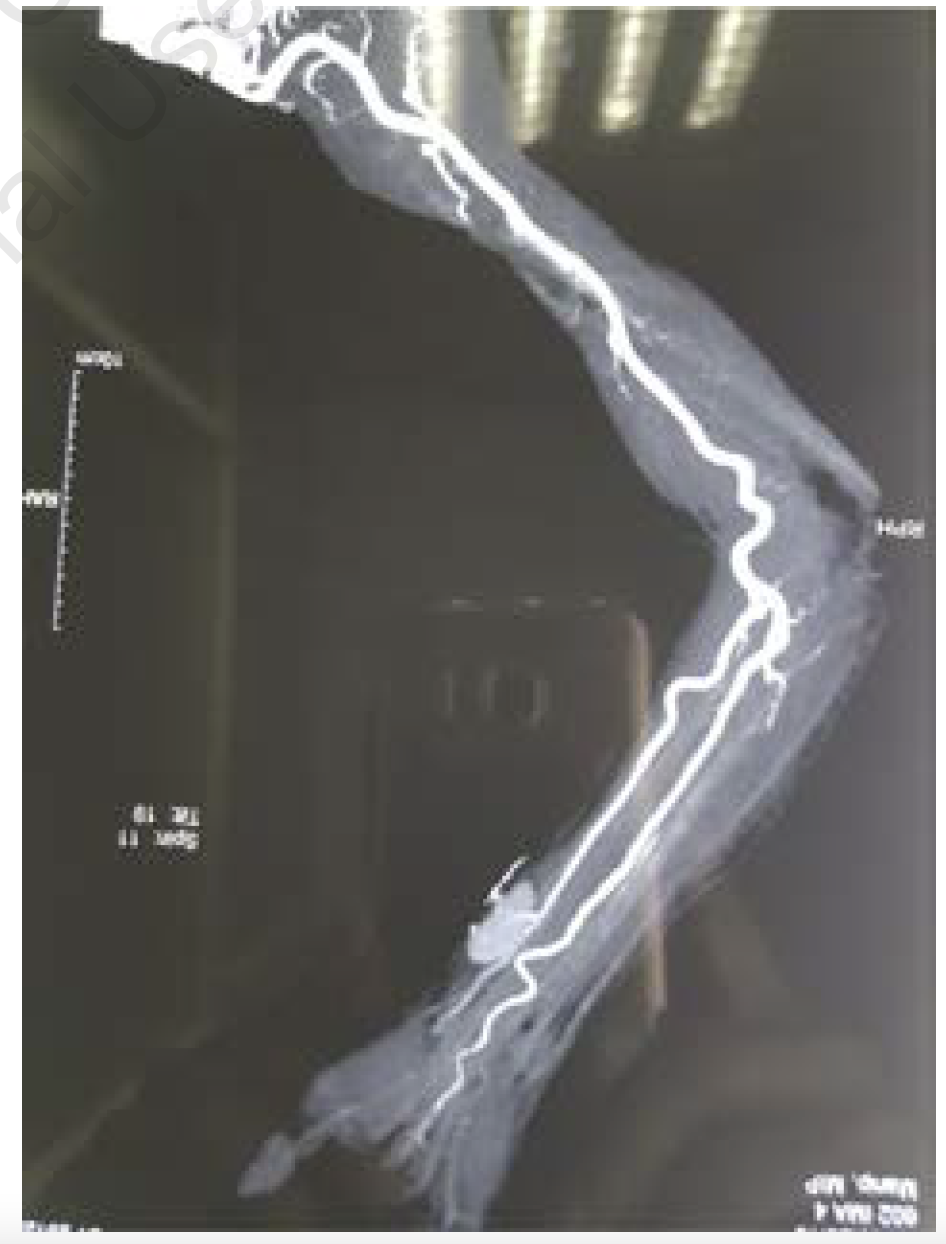

Doppler of the right radial artery revealed a 1.4 x 4 cm mass from the distal end of the right radial artery with a typical yin yang pattern of color flow suggestive of a radial pseudoaneurysm. CT angiogram of the radial artery showed that the right radial artery was normal in course and caliber. Contrast filled an out-pouching measuring 1.7 x 2 x 3.3 cm seen about 5 cm proximal to the radial styloid process. The neck of the pseudoaneurysm measured 2.3 mm. No extravasation or filling defects or thrombus were noted (as per the radiologist). In Figure 3, a thrombus can be seen outside the pseudoaneurysm. The right superficial and deep palmar arches were normal, as were the right ulnar and right brachial arteries.